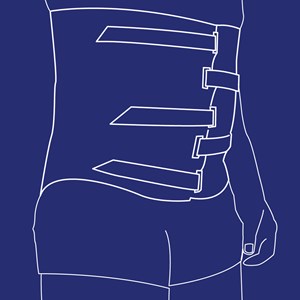

Abdominal korset

Type: pdf

Størrelse: 1129 KB